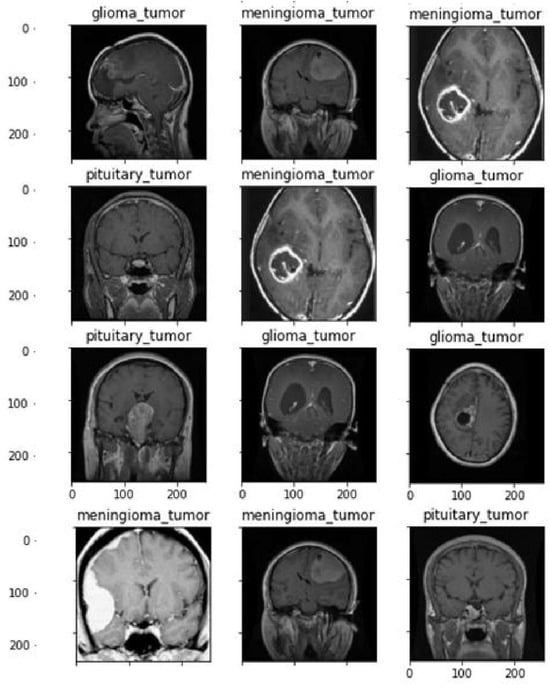

4.2. Dataset